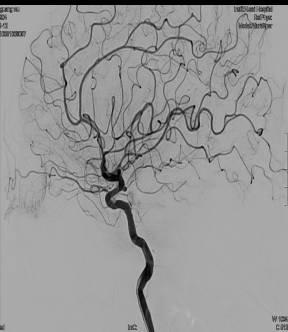

DSA:基底动脉尖端分叶状小动脉瘤,左侧颈内动脉床突上段动脉瘤。

基底动脉尖1.8mmx3.2mm囊性显影,分叶状动脉瘤。

再次行左侧股动脉穿刺,引入另一根指引导管进入右侧颈内动脉,将一根Prowler Select Plus支架导管通过右侧颈内动脉、后交通动脉、右侧大脑后动脉到达左侧大脑后动脉P2段。再将SL-10微导管通过置入左侧椎动脉的另一根指引导管到达动脉瘤腔,选择Enterprise 4.5mmx14cm支架跨瘤颈放置,采用半释放技术,选择一枚Delta paq 1.5mmx4cm栓塞动脉瘤两个瘤囊。

三月后复查动脉瘤未复发,载瘤动脉通畅。